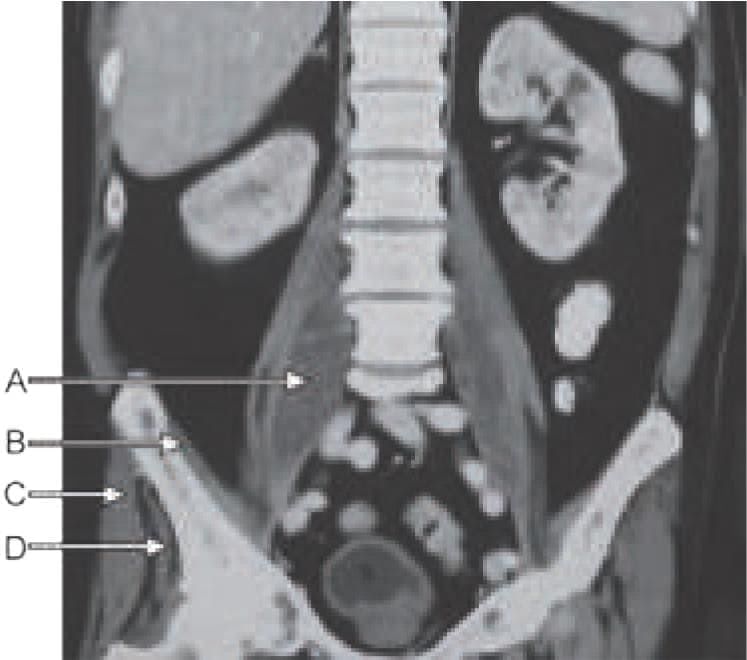

In CT scan of liver, identify the arrow marked segment: (INI-CET Nov 2022)